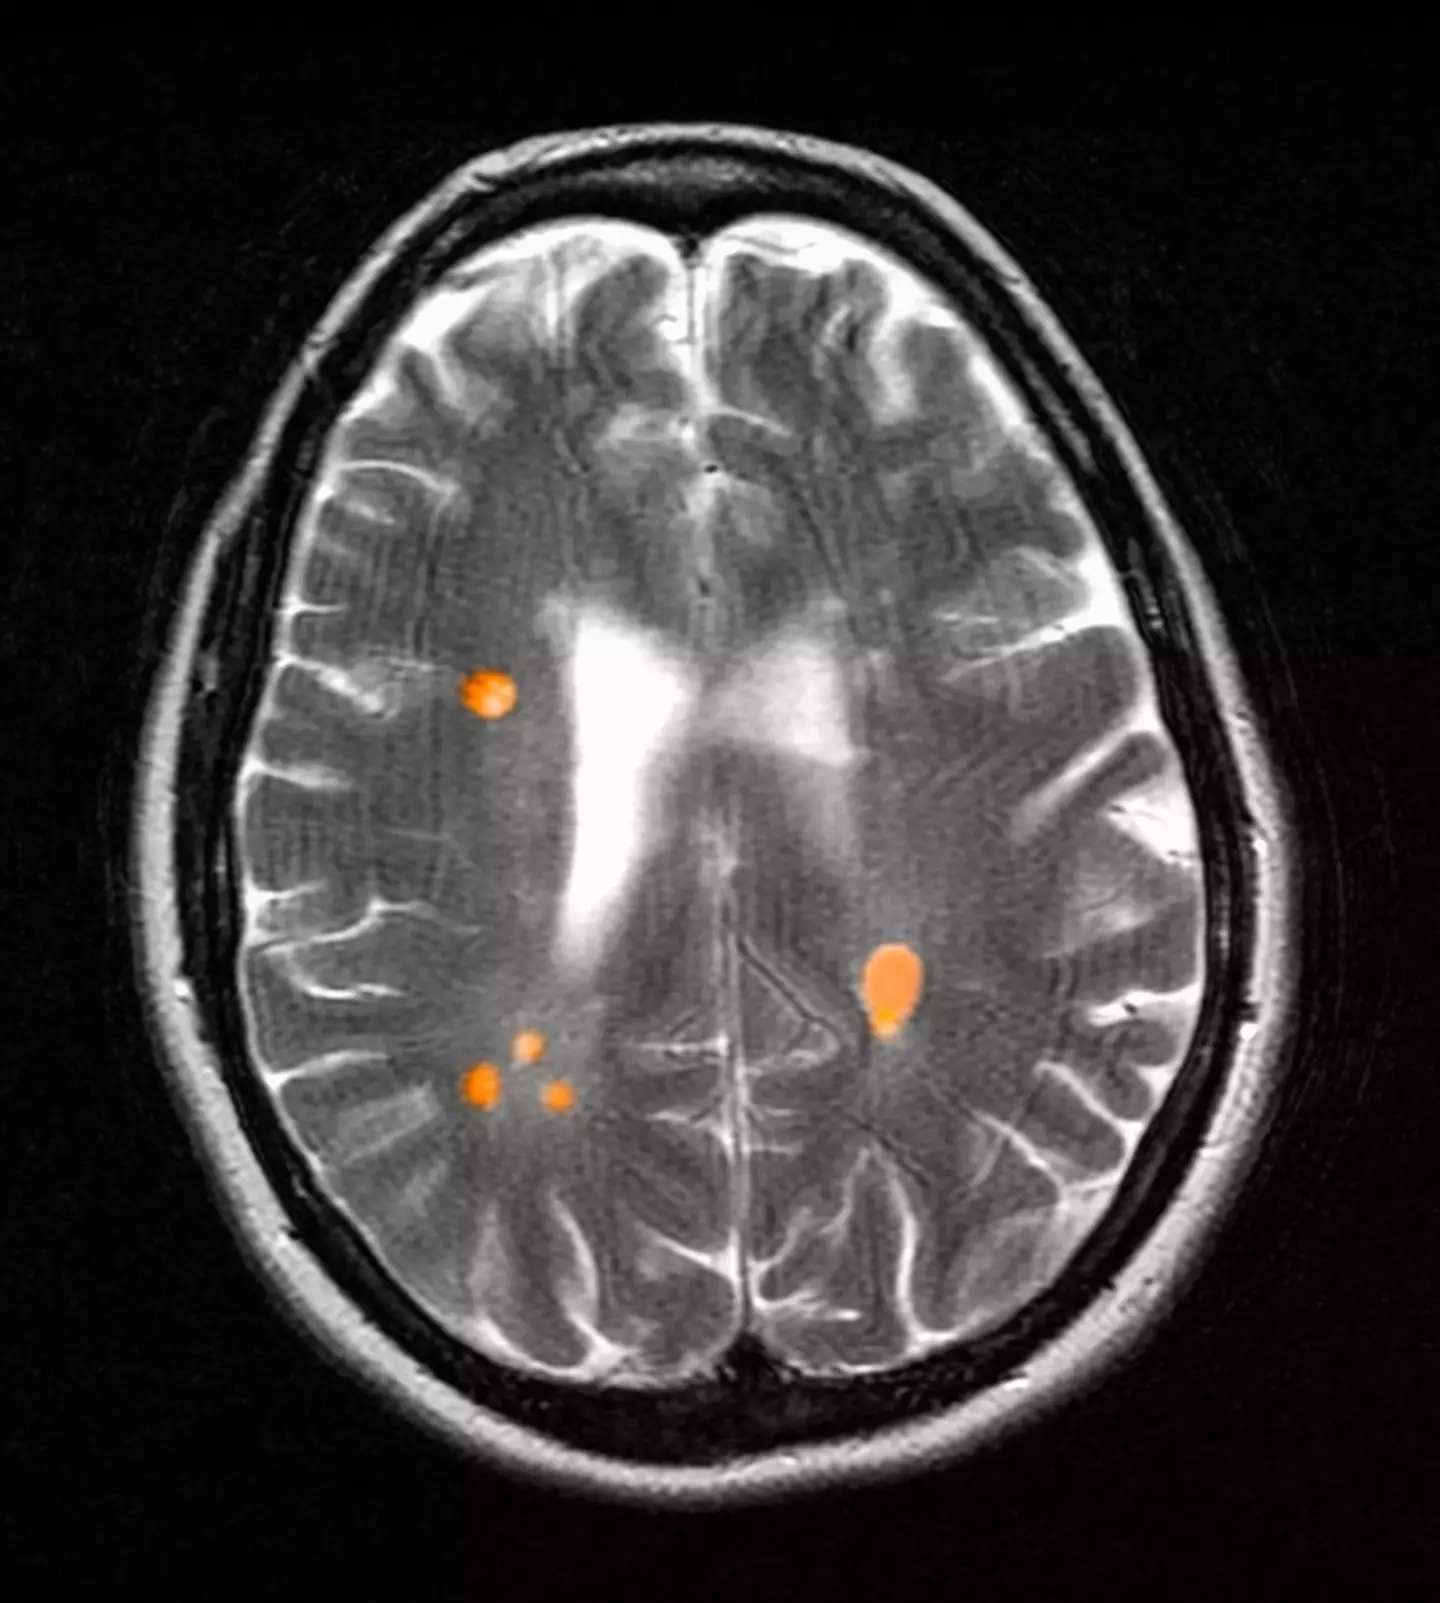

In the children who were exposed to parental smoke, the researchers could see associations considering total brain and thalamic volumes were a higher MS-genetic risk, which is associated with lower total brain and thalamic 'grey matter' volumes.

This shows that children who are subjected to parental smoke, who have higher genetic burden for MS, show lower brain volumes compared to children who are not exposed to tobacco smoke.

"These are also two brain matter volumes that are decreased in MS patients," the researchers added.